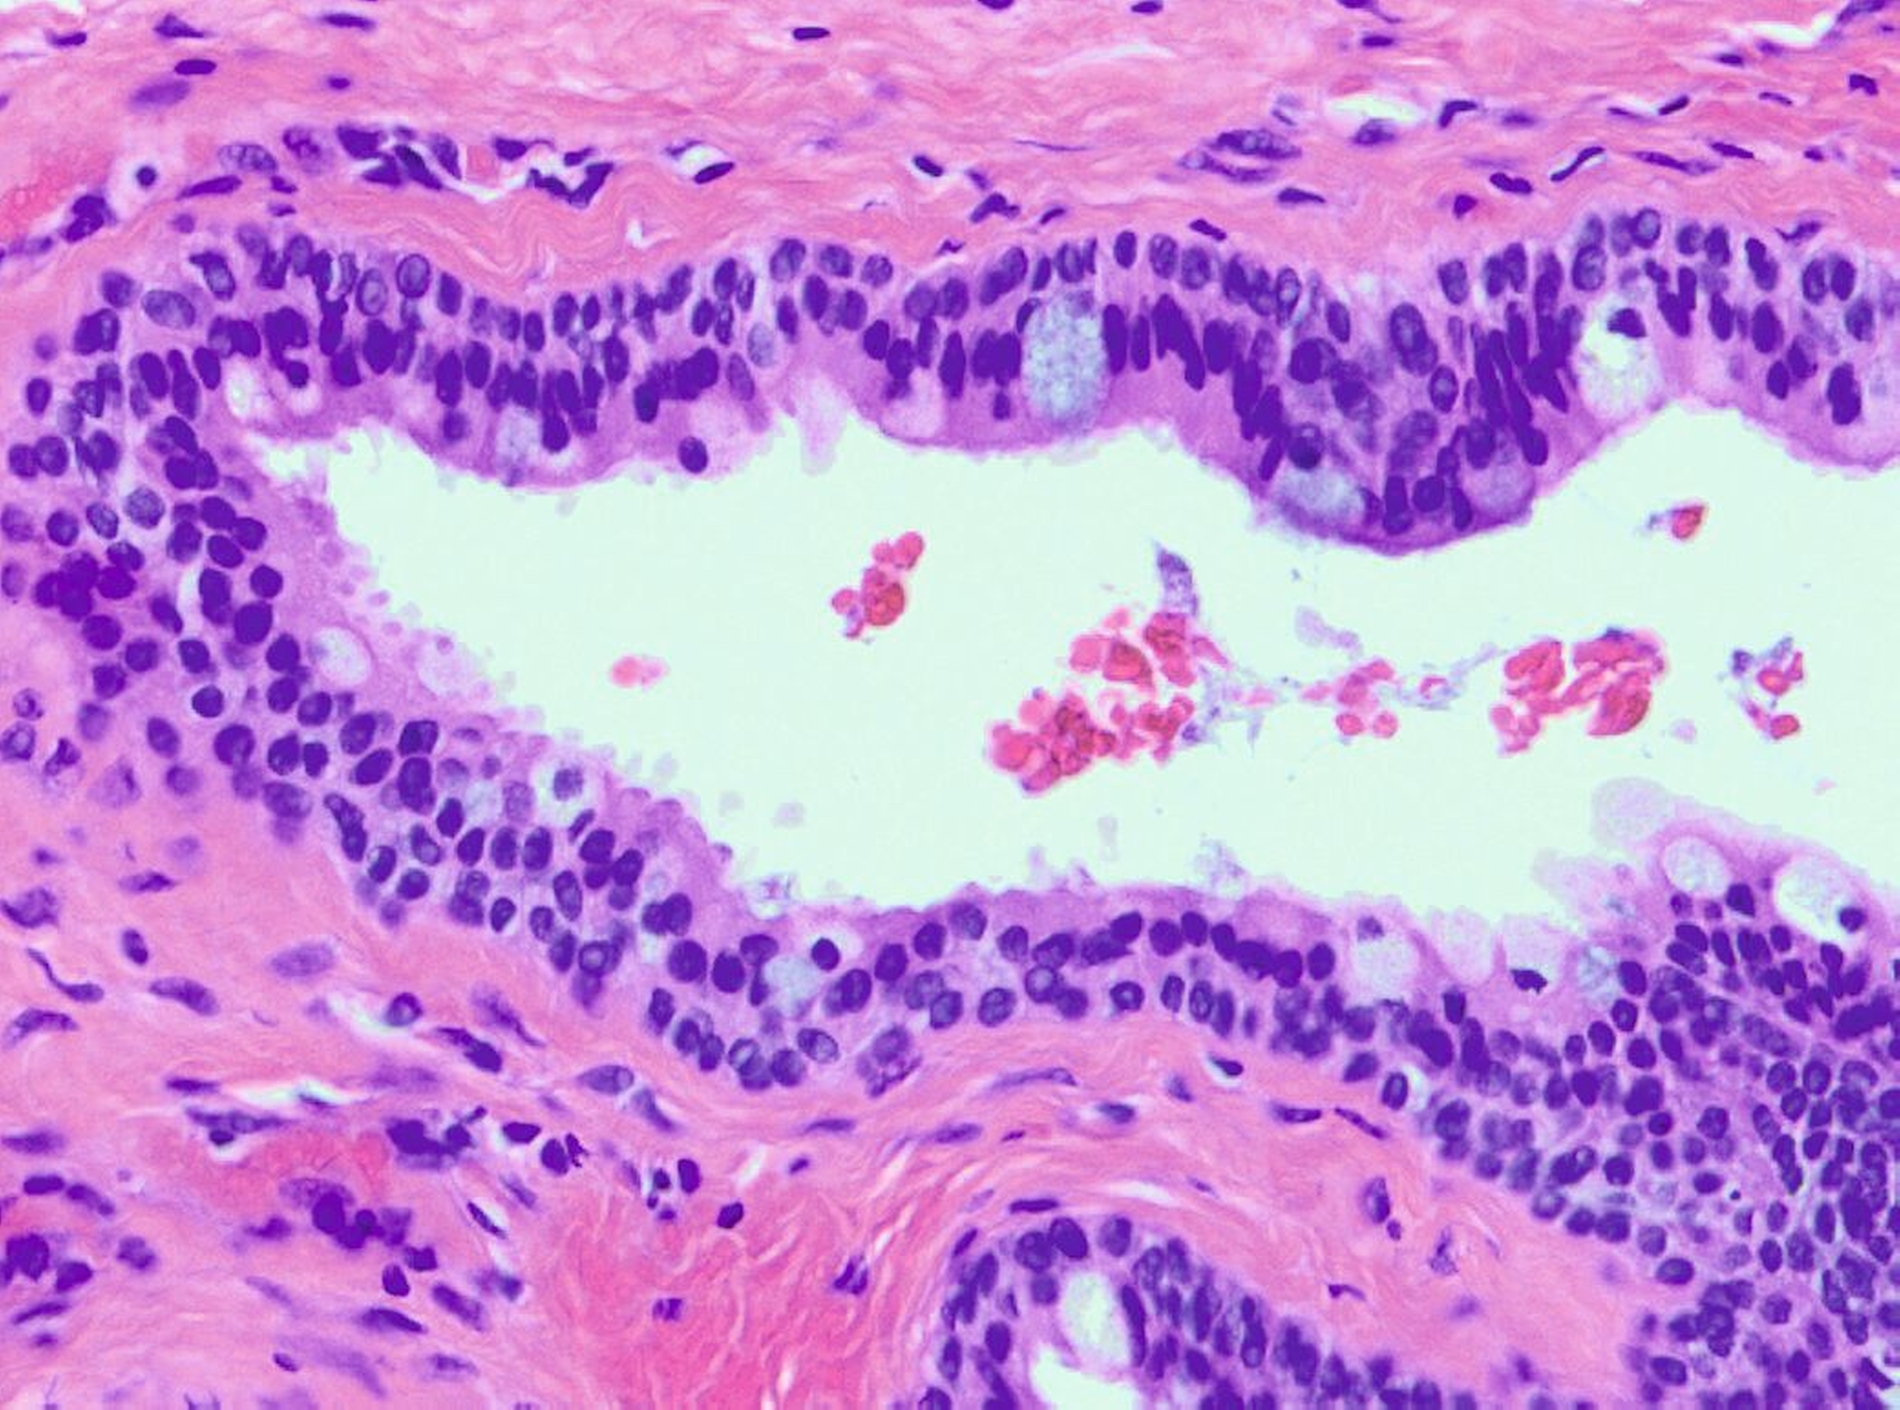

Im Ergebnis der pathohistologischen Begutachtung zeigten sich fibrosierte Zystenwandanteile, die mit respiratorischem Epithel ausgekleidet waren (Abbildung 3). Die zytologische Diagnostik des Punktats erbrachte ein zellloses, amorphes Sekret ohne atypische Zellelemente und ohne Anhalt für Malignität. Anhand der Klinik und des pathohistologischen Befunds wurde die Diagnose einer nasolabialen Zyste gestellt.

Die nasopalatinale Zyste ist die häufigste der dysgenetischen, nicht odontogenen Kieferzysten. Diese imponiert klinisch als mediane Schwellung unmittelbar dorsal der Schneidezähne und entsteht aus Epithelresten des Ductus Incisivus [Dedhia et al., 2013]. Als Besonderheit findet sich häufig eine Auskleidung mit respiratorischem Flimmerepithel [Swanson et al., 1991]. Eine seltene Variante ist die mediane Gaumenzyste, die klinisch als Schwellung in der dorsalen Gaumenmitte imponiert und mit einem Verhältnis von vier zu eins deutlich häufiger bei Männern auftritt [Hadi et al., 2001].

Der Zystenbalg hat häufig eine epitheliale Auskleidung mit Flimmerepithel und ist dadurch von entzündungsbedingten Zysten abgrenzbar.